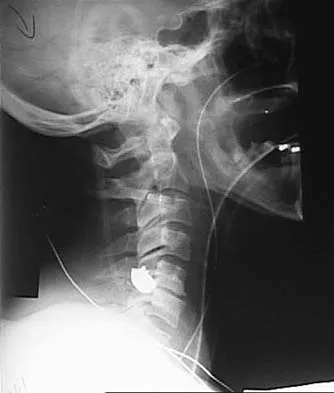

A 19-year-old woman reports persistent neck pain for 2 years. Pain is relieved with aspirin. A bone scan shows intense uptake in the superior, posterior portion of the C3 vertebral body. A sagittal CT reconstruction is shown in Figure 5. Treatment should consist of

Explanation

The CT scan shows an osteoblastic nidus pathognomic for an osteoid osteoma. Surgical treatment should include an en bloc excision of the lesion. Surgical treatment is not mandatory because the lesion often becomes asymptomatic over time. This lesion is not amenable to radiofrequency ablation due to its proximity to the spinal cord. A complete corpectomy is not necessary to adequately resect the lesion, as only the nidus needs to be removed. Radiation therapy and antibiotics are not appropriate treatments for an osteoid osteoma. Posterior C2-C3 fusion will not address the pathology. Spivak JM, Connolly PJ (eds): Orthopaedic Knowledge Update: Spine 3. Rosemont, IL, American Academy of Orthopaedic Surgeons, 2006, pp 351-366.